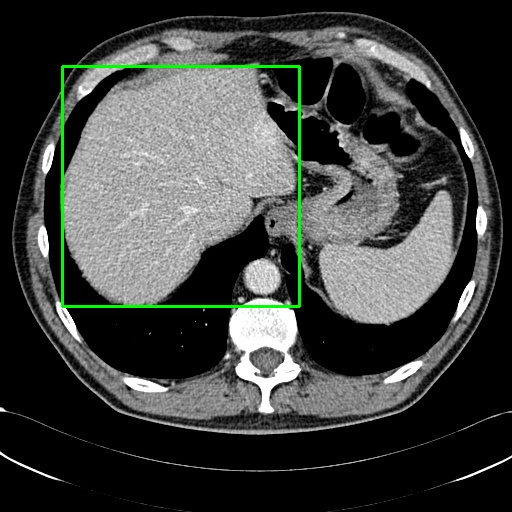

We use ROIs to provide visual annotations for each image, primarily focusing on pathological findings such as lesions, inflammation, neoplasms, infections, and other abnormalities. In cases without such abnormalities, the ROIs generally mark the primary object or organ in the image, as illustrated in  Figure 10. When multiple organs are relevant for disease diagnosis, the ROIs aim to cover several regions associated with the disease, providing detailed analysis of each affected area, as shown in  Figure 11.

We employ appropriate strategies to locate ROIs for images paired with different annotations. For datasets that already include localization annotations, such as segmentation masks or bounding boxes, we derive the ROIs from these paired annotations. Specifically, bounding boxes are directly used as the ROIs, while segmentation masks are converted to ROIs by creating the smallest bounding box that covers the mask. When such localization annotations are not available, we apply corresponding pretrained expert models to generate ROIs. More details about the selection of expert models are provided in Appendix D. Examples of generated ROIs from various modalities using corresponding models are demonstrated in Figure 6. For modalities such as X-ray and MRI scans viewed from the z-axis, our ROI localization employs a coordinate system relative to the human body, resulting in a left-right reversal in the image representation.

Incorporating ROIs as the guidance facilitates MLLMs to conduct a detailed analysis and generate multigranular textual descriptions. As demonstrated in Figure 4, description generated without guidance of ROIs is limited to a brief global overview of the image. In comparison, with ROIs, generated description contains local analysis regarding the abnormal region and its correlations to other regions.